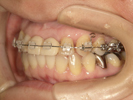

30代女性

事故のため、前歯を2本失いました。

インプラントと矯正治療をしました。

| 治療前 | ||

| インプラント後、仮歯を入れました。 | ||

| 矯正設置を着用し、歯列矯正を行いました。 | ||

| 治療後 | ||